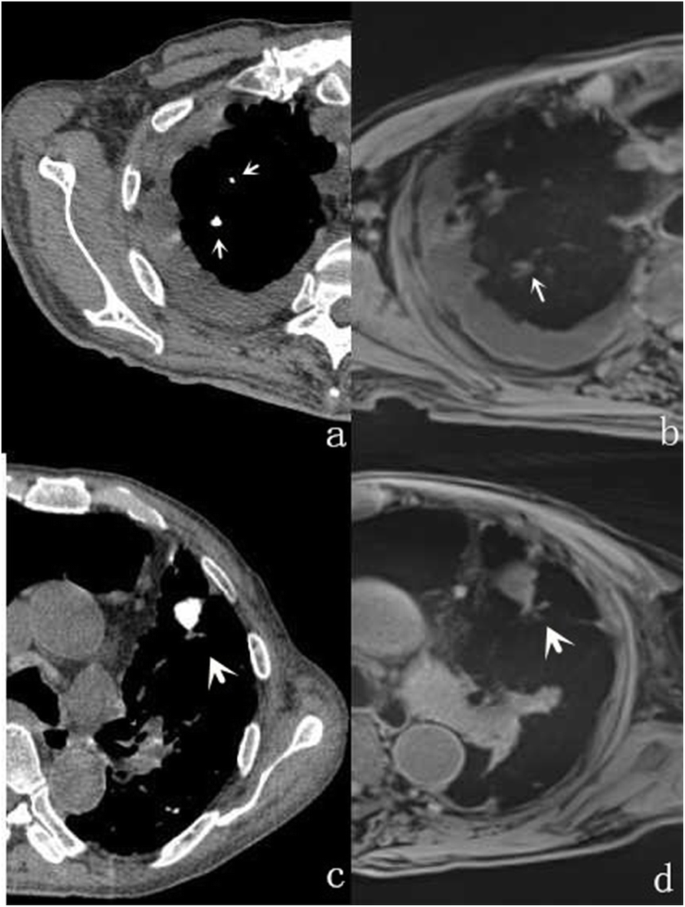

A 65-year-old male with lung adenocarcinoma and pulmonary metastasis. MSCT demonstrates a nodule (star) with pleural indentation (a and b):. r-VIBE imaging shows the nodule with clear boundaries (c):; however, it is not well depicted on water signal-suppressed C-VIBE (d) or in-phase C-VIBE images (e). Multiple nodules in the lungs can also be seen (a and b), among which, nodules 3.2 mm (thick arrow) and 2.8 mm (fine arrow) in diameter are clear on r-VIBE (c), but unclear on C-VIBE images (d and e)